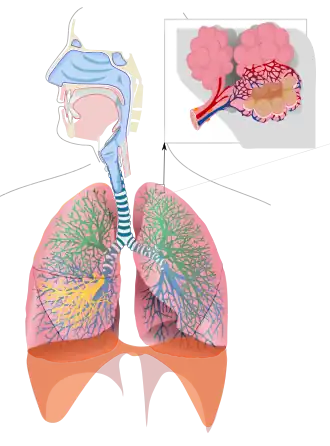

Inhalation exposure

Inhalation is a major route of exposure that occurs when an individual breathes in polluted air which enters the respiratory tract. Identification of the pollutant uptake by the respiratory system can determine how the resulting exposure contributes to the dose. In this way, the mechanism of pollutant uptake by the respiratory system can be used to predict potential health impacts within the human population.[1]

Uptake of particulate pollutants

Prediction of the location of particle deposition into the respiratory tract depends on the size and type of particle. Coarse particles, originating from natural sources such as dust, sand and gravel, tend to deposit in the nasal-pharyngeal region. Fine particles, derived from anthropogenic sources such as fossil fuels and smoking, typically deposit in the pulmonary region. Most gas exchange occurs in the pulmonary region due to the alveoli, which contain a large surface area.